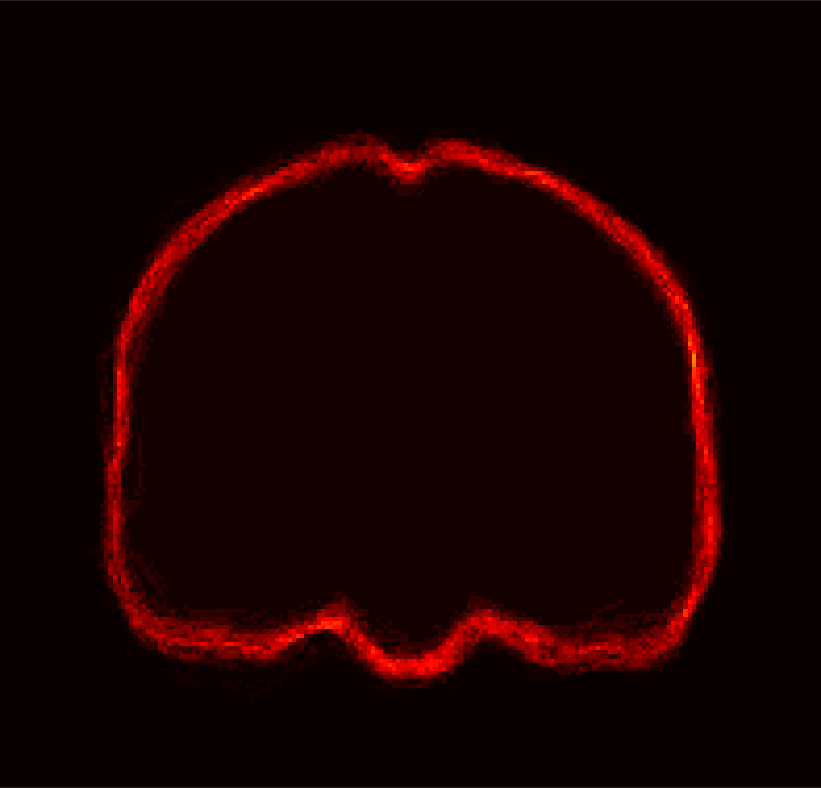

For IBSR, segmentations of the brain images into white matter, gray matter and cerebrospinal fluid (CSF) are provided. While, in principle, the union of the segmentations of white matter, gray matter and CSF should represent the desired brain mask, this is not exactly the case (see Fig. 2). To alleviate this issue for each segmentation, we use morphological closing to fill in remaining gaps and holes inside the brain mask and, in particular, to disconnect the background inside the brain mask from the surrounding image background. The structuring element for closing is a voxel and its 18 neighborhood333The 18-voxel connectivity is also used for other morphological operations in this manuscript.. We then find the connected component for the background and consider its complement the brain mask. Fig. 2 shows the pre-processing result after these refinement steps, compared to the original IBSR segmentation (i.e., the union of white matter, gray matter, and the CSF).

[Uncaptioned image] [Uncaptioned image] [Uncaptioned image]

(a) (b) (c)

Figure 2: Example coronal slice of (a) an IBSR MR brain image, (b) the corresponding original IBSR brain segmentation (i.e., union of white matter, gray matter and CSF) and (c) the refined brain segmentation result.